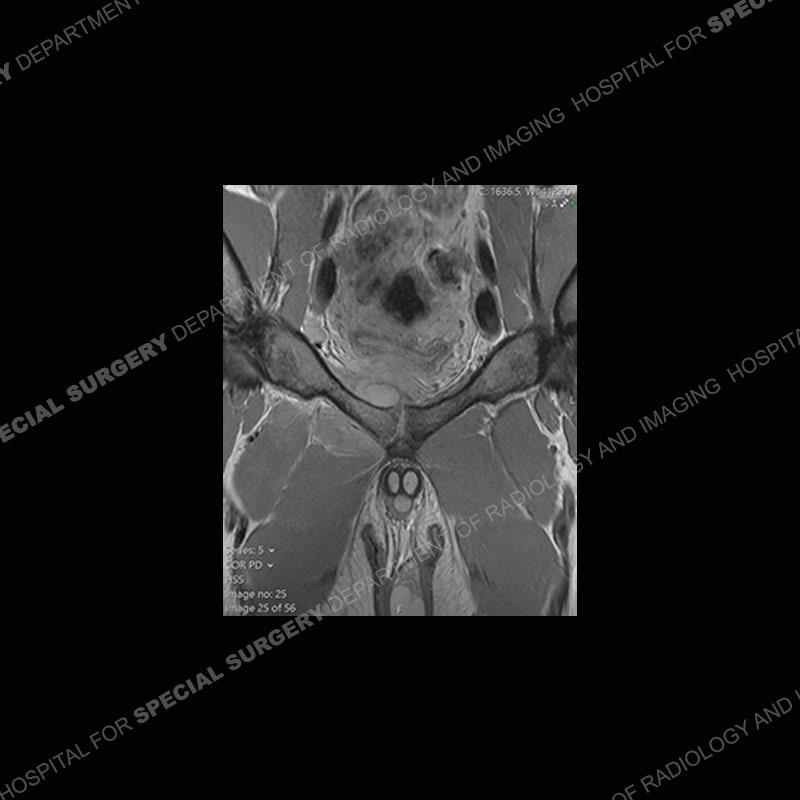

Radiographs did not demonstrate any clear abnormality. The MRI shows markedly abnormal signal of the right superior pubic ramus and abnormal signal/”mass” extending into the adjacent soft tissue. The inferior articular surface of the ramus showed what was thought to be bony destruction. CT examination shows a destructive process of the right superior pubic ramus.

Subsequent MRI in a very short time interval shows markedly increased abnormality of the ramus and increased edema and “mass” of the soft tissue. Post contrast imaging shows multiple, rim enhancing collections of the soft tissue and similar albeit less conspicuous enhancing collection of the ramus.

Diagnosis: Osteomyelitis and Soft Tissue Abscess